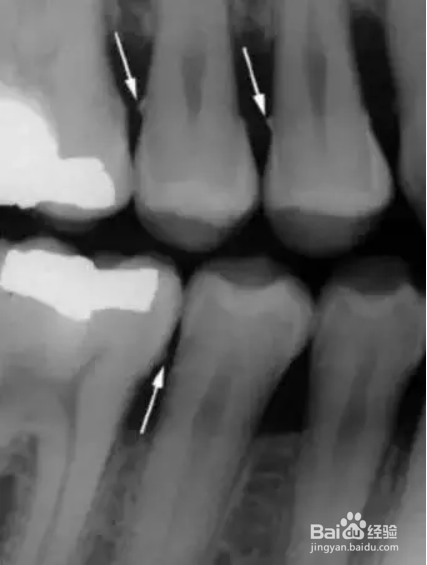

1、除了临床检查,X 光片也是必不可少的。在牙周检查里,最常用的是根尖片和咬翼片,有时候再加上全景片。

3、垂直咬翼片更适合牙周检查。因为牙周病患者通常有骨吸收,如果吸收严重,水平咬翼片可能没法显示牙槽嵴,而这时垂直咬翼片就显示了其优点。